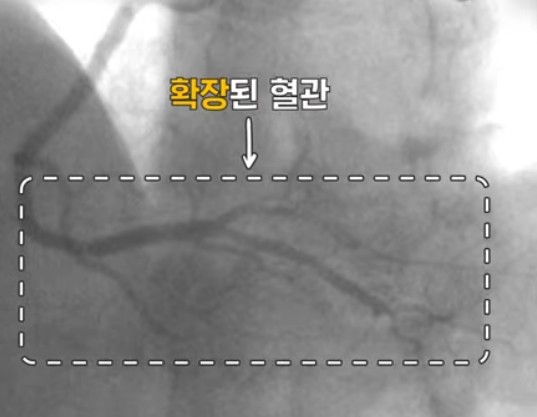

자극이 없어지면 혈관은 다시 정상을 회복하는데 마치 자다가 근육에 쥐가 났다가 풀리는 증상과 비슷하다고 합니다.

변이형 협심증을 진단하기 위해서는 경련유발검사를 시행하며 치료는 약물 치료로 대부분 증세 없이 지내실 수 있지만 대게 1년 이상 투약이 필요하고 일부 환자는 투약을 줄이거나 , 투약을 중지하는 경우도 있습니다만 평생 복용해야 하는 경우도 있습니다.